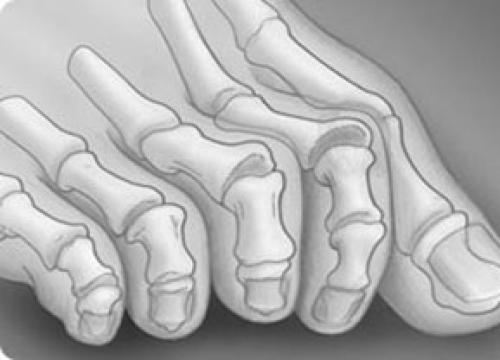

Молоткообразная деформация 2, 3, 4-го пальцев стопы – деформация (чаще 2, 3-го), при которой пальцы искривляются в виде молотка. При этой патологии проксимальная фаланга разогнута в плюснефаланговом суставе, средняя согнута в межфаланговом суставе.

Изолированно молоткообразная деформация встречается редко. Чаще сочетается вальгусным отклонением первого пальца стопы и поперечным плоскостопием.

Когтеобразная (крючкообразная) деформация – палец искривляется в виде крючка. Проксимальная фаланга разогнута в плюснефаланговом суставе, остальные 2 согнуты в межфаланговых.

Палец-«колотушка» — искривление в виде молоточка. Ногтевая фаланга согнута в дистальном межфаланговом суставе.

Все вышеперечисленные виды искривлений могут быть мягкими (нефиксированными) и фиксированными (ригидными).